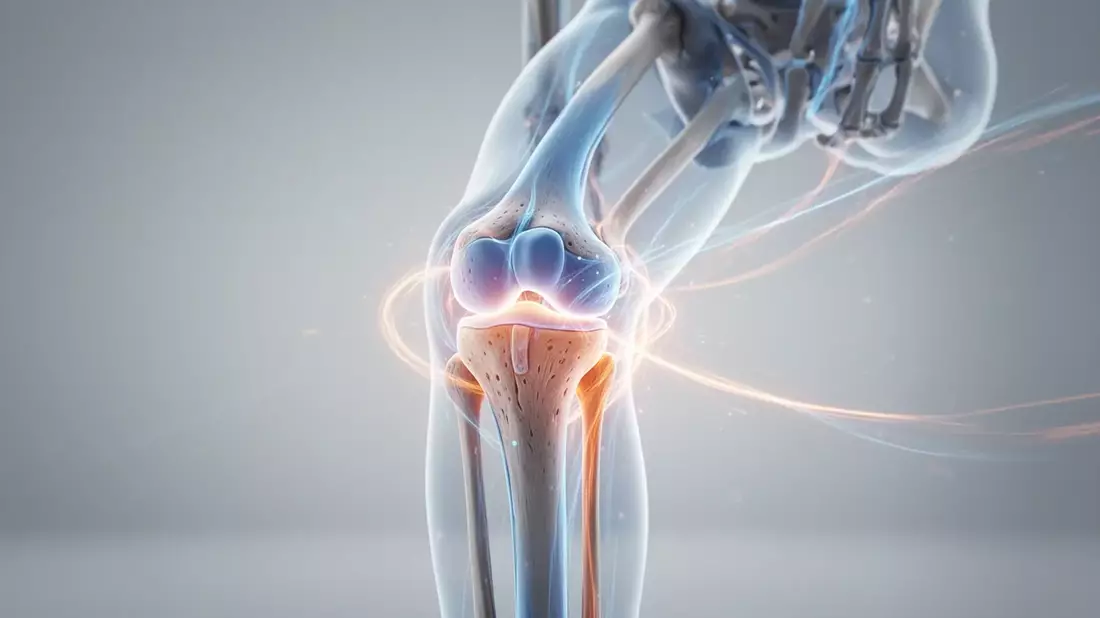

Paradigmenwechsel in der Arthrose-Forschung

Am 28. April erhielt Prof. Dr. Frank Roemer vom Uniklinikum Erlangen den OARSI Clinical Research Award. Seine MRT-Forschung verändert das Verständnis von Arthrose grundlegend. Die Erkrankung gilt heute nicht mehr als passiver Gelenkverschleiß, sondern als komplexer, prozesshafter Zustand des gesamten Gelenks.

Das Ziel: Therapien entwickeln, die nicht nur Symptome lindern, sondern die Gelenkstruktur aktiv verändern können.

Was hinter akuten Knieschmerzen steckt

Am 29. April identifizierten Experten zahlreiche Ursachen für Schmerzen beim Strecken des Beins. Neben Meniskusschäden und Knorpelverschleiß spielen auch retropatellare Arthrose, muskuläre Überlastungen und Fußfehlstellungen eine Rolle.

Krafttraining als Gelenkschutz

Die Muskulatur entlastet das Kniegelenk – das wird in der Fachdiskussion immer deutlicher. Knieschmerzen entstehen oft nicht durch das Gelenk selbst, sondern durch schwache Sehnen oder verkürzte Muskeln.